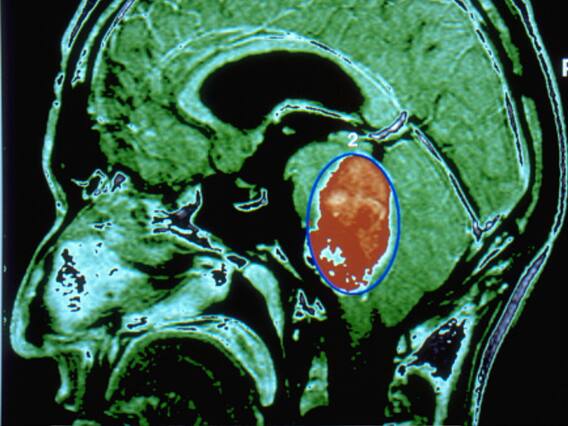

New Delhi: Every year on June 8, World Brain Tumour Day is observed to create awareness about brain tumours and how it affects individuals. A lump or collection of aberrant brain cells is known as a brain tumour. They are of two types: Benign and malignant. Benign brain tumours are non-cancerous and usually have slow growth. They are unique, and they typically don't spread to other areas. However, because they compress and harm a portion of the brain they can cause severe malfunction.